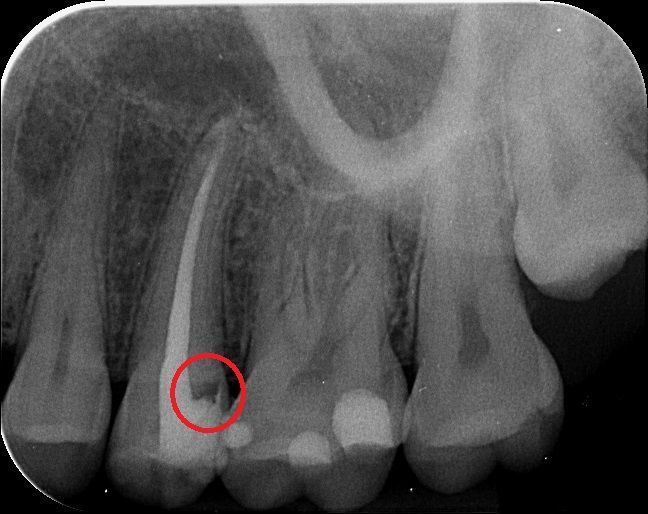

Unsere erfahrenen Zahnärztinnen setzen moderne digitale Röntgengeräte ein. So können aussagekräftige Röntgenbilder erstellt werden. Zudem profitieren Sie von einer deutlich geringeren Strahlenbelastung.